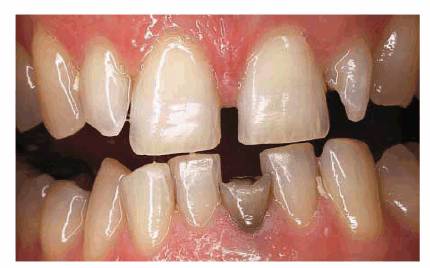

PROBLEM: This 39-year-old individual presented with diastemas between

had a marked overbite and fracture of a mandibular central incisor (Figure 23-4A

Figure 23-4A: This 39-year-old man was unhappy with his diastema, deformed laterals, and mandibular fractured incisor.

TREATMENT: A removable maxillary appliance with finger springs was

constructed to orthodontically reposition the central incisors together (Figure 23-4B). A mandibular lingual appliance

was also used to upright the molars to regain lost vertical dimension and

realign the crowded mandibular anterior teeth. After completion of orthodontic

treatment, the maxillary central incisors were splinted together with composite

resin to prevent future drifting and reformation of the diastema (Figures 23-4C

and D). The

adjacent maxillary lateral incisors were crowned to assist the stabilization of

the central incisors and restore symmetry to the maxillary arch, eliminating

their "peg-lateral" shape (Figure 23-4E). In addition, the mandibular left

central incisor was crowned. The final smile achieved improved esthetics,

health, and function (Figure 23-4F

Figure 23-4B: A removable maxillary appliance with finger springs was used to bring the central incisors together.

Figure 23-4C and D: The maxillary central incisors were bonded together with composite resin to help retain them in their new position.

Figure 23-4E and F: The adjacent maxillary lateral incisors were crowned to help hold the central incisors in place and restore symmetry to the maxillary arch. The mandibular left central incisor also was crowned to complete the esthetic result.

RESULT: The success of this case is based

on a close working relationship with the orthodontist to accomplish necessary

repositioning before restorative procedures are begun. The final esthetic

result could not have been achieved by crowning the four incisors alone. If

orthodontics had not been employed, either the central or lateral incisors

would have necessarily been overcontoured; in addition, the overbite would not

have been corrected to any appreciable extent.